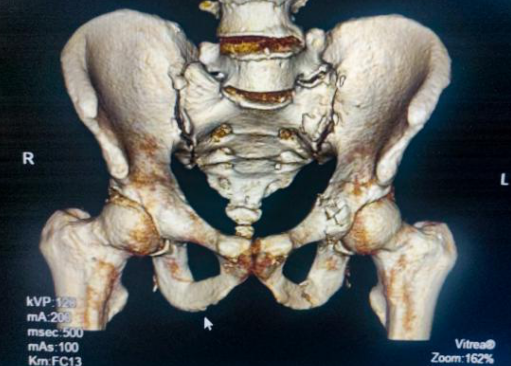

老人入院后完善了相关检查诊断:骨盆多发性骨折、左侧髋臼骨折、左侧耻骨上下支骨折、左侧髂骨骨折、左侧骶骨骨折、多发肋骨骨折。

术前